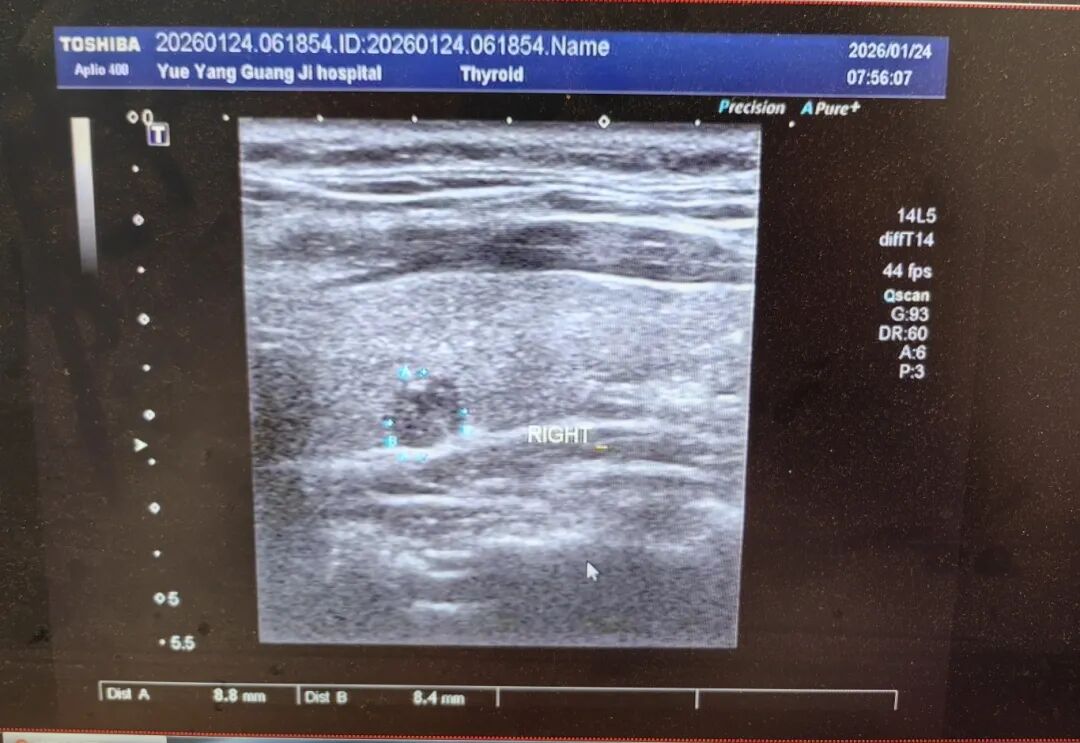

真实案例:35岁男性结节达5类,消融术助其摆脱顾虑

35岁的李先生(化名)正是这次义诊的受益者之一。近期,李先生在体检中被查出甲状腺结节,听说这次北京超声专家过来,特请专家进一步检查,确定为双侧甲状腺结节,分类为5类,这意味着双侧结节恶性风险高,虽然结节大小接近1cm,若不及时干预,病情可能进一步进展,传统治疗需开刀切除全部甲状腺,术后需要终身服用药物治疗。

结合李先生的年龄、结节大小、性质及身体状况,综合评估后建议其采用甲状腺消融术。李先生和家人商量后选择了甲状腺射频消融术。